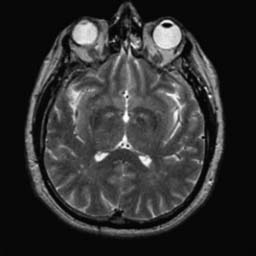

To demonstrate the effectiveness and efficiency of the proposed image fusion method , we conduct a set of comparative experiments on three image datasets. The first is composed by 8 pairs of multi-modal medical images and the second one contains 15 pairs of multi-focus gray or color natural images. These two datasets are often used in many related papers and some examples are shown in Figure 3(a) and Figure 3(b). The third one is a new multi-focus cervical cell image dataset collected by ourselves, which consists of 15 groups of color images and each group contains a series of multi-focus cervix cell images with size of or , etc. Some source examples are shown in Figure 3(c). Our source code implemented in C++ along with the new multi-focus cervical cell image dataset is available online.

We first evaluate the performance of the proposed method under varying total number of octaves and number of layers sampled per octave. The fused images of a pair of multi-modal medical images with different and are shown in Figure 4. In this example, on the one hand, when only 1 or 2 octaves are involved in constructing the DoG pyramid, the fused images fail to keep the integrity information of large size objects (e.g. eyeballs), while by increasing the value of , the integrity information of eyeballs is preserved. On the other hand, although not as significant as the increase of octave numbers , the fused image can contain more details by the increase of layer numbers . The corresponding objective quality metrics are shown in Figure 5. As shown in Figure 5(a), most of the metric values are improved as the number of octaves increases with the fixed layer numbers 3 in the global tendency and each of them tends to be stable when the number of octaves is 5. To get a relatively good quality from Figure 5(b), we can notice that some of the metric values can get a good performance when the number of layers is 3, such as the MI, SSIM, QI and VIF, though there are only a little change of all the metric values by increasing the number of layers with the fixed octave numbers 5. Because it will result in more computation burden with the increase of the value and , and for different kinds of source images, there are different performance with the diverse parameter settings. To get a trade-off between them in our experiments, we set for the multi-modal dataset, for the natural datasets and for the multi-focus cell dataset, respectively.

Figure 6 shows the fused images obtained by different methods with the multi-modal source images shown in Figure 3(a). As shown in these figures, the proposed method can produce images which preserve the complementary information of different source images well. Moreover, due to the scale-invariant structure saliency selection, our method can keep the integrity information of large size objects and the visual details simultaneously. Although the fused image generated by other methods can also capture the details to some extent, all of them fail to keep the integrity information of large size objects such as the eyeballs. Furthermore, from Figure 6(k)-6(t), the DTCWT, GFF, IM and NSCT methods may decrease the brightness and contrast while the proposed method can preserve these features and details without producing visible artifacts and brightness distortions.